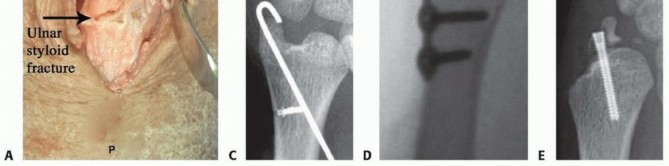

Open Reduction Internal Fixation of Ulnar Styloid Fracture Indicated in the treatment of the unstable DRUJ after radius fixation with large ulnar styloid base fracture Two different approaches can be used: An extensile approach is described for open TFCC repair. This has the advantage of assessing whether the TFCC has torn off the ulnar styloid fragment. Alternatively, while offering less visualization, an incision can be made immediately over the ulnar styloid, resulting in less disruption to stabilizing soft tissue structures of the DRUJ. This incision is begun 1 cm distal to the styloid and carried proximally to the ulnar neck. Blunt dissection distal to the ulna styloid is performed to identify the dorsal ulnar cutaneous branch, which passes volar to dorsal, most often immediately distal to the ulnar styloid. Typically, there is soft tissue interposed at the fracture site and this is cleared with a hemostat or dental pick. The forearm is then rotated through pronosupination until the styloid fracture reduces to the fracture footprint. A 3.5-mm toothed drill guide fits nicely over the styloid tip and can be used to compress the styloid, whereas two 0.045 or 0.054-inch smooth stainless steel pins are driven through both the styloid and the far ulnar cortex. The pins are then backed out of the far ulnar cortex slightly. (TECH FIG 4A).

TECH FIG 4 • Ulnar styloid fracture fixation. A. The distal ulna is exposed at the ulnar styloid and a 3.5-mm drill guide is used to reduce the fracture and to pass K-wires. B. Anteroposterior (AP) radiograph of a tension band open reduction internal fixation (ORIF). C. Tension band construct with a suture anchor. D. ORIF with plate and screw construct. E. Loss of fixation using headless compression screw. A transverse (dorsal to volar) 2-mm drill hold is made proximally through the ulnar neck, and a 27-gauge wire is placed through the TFCC at its insertion on the ulnar styloid. A figure-of-eight bend is made, and one limb is passed volar to dorsal through the transverse bone hole, whereas the other is passed dorsal to volar. The wire is then twisted to tension, and the pins are bent and cut. The bent tips are pointed radially and driven into the styloid with a small bone tamp, capturing the wire (TECH FIG 4B). Alternatively, after placing the pins through the ulnar styloid, a 2-0 suture anchor can be placed in the ulnar neck and the sutures passed in opposite directions around the styloid. The limbs are tied down to the medial ulnar shaft, and the pins are bent and cut as previously discussed (TECH FIG 4C). Plate and screw construct may also be used for buttress effect, but implant prominence must be considered (TECH FIG 4D). Headless compression screw fixation is advocated by some. We have noted frequent failure and malreduction with this technique. If screw fixation is used, bicortical fixation is recommended (TECH FIG 4E). If the DRUJ is still unstable, proceed with radioulnar transfixation pinning. Wound closure, sterile dressings, and long posterior splint are applied.